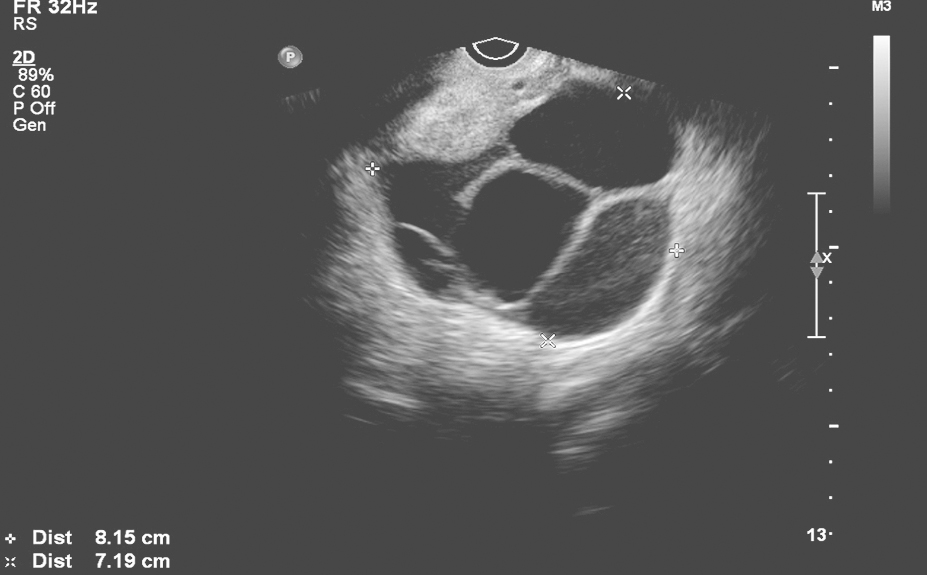

女性盆腔超声、MRI及男性睾丸超声有助于协助明确性腺有无形态学异常。如图2所示为北京协和医院诊治的1例女性FGAs的盆腔MRI,可见巨大卵巢囊肿;图3所示为北京协和医院诊治的1例女性FGAs的盆腔超声,可见多发卵巢囊肿。

图3 1例女性垂体FGA患者的盆腔超声可见多发卵巢囊肿